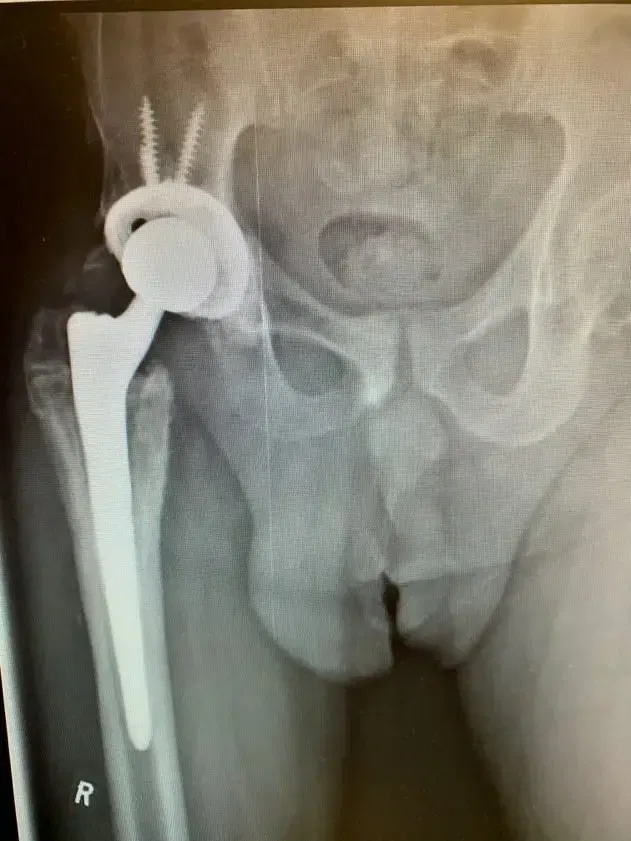

La paciente es una mujer de 75 años que acudió a nosotros con dolor intenso en la cadera izquierda tras someterse a una fijación interna de reducción abierta (ORIF) de la cadera izquierda. El paciente vino con radiografías para revisar, como se muestra a continuación,...